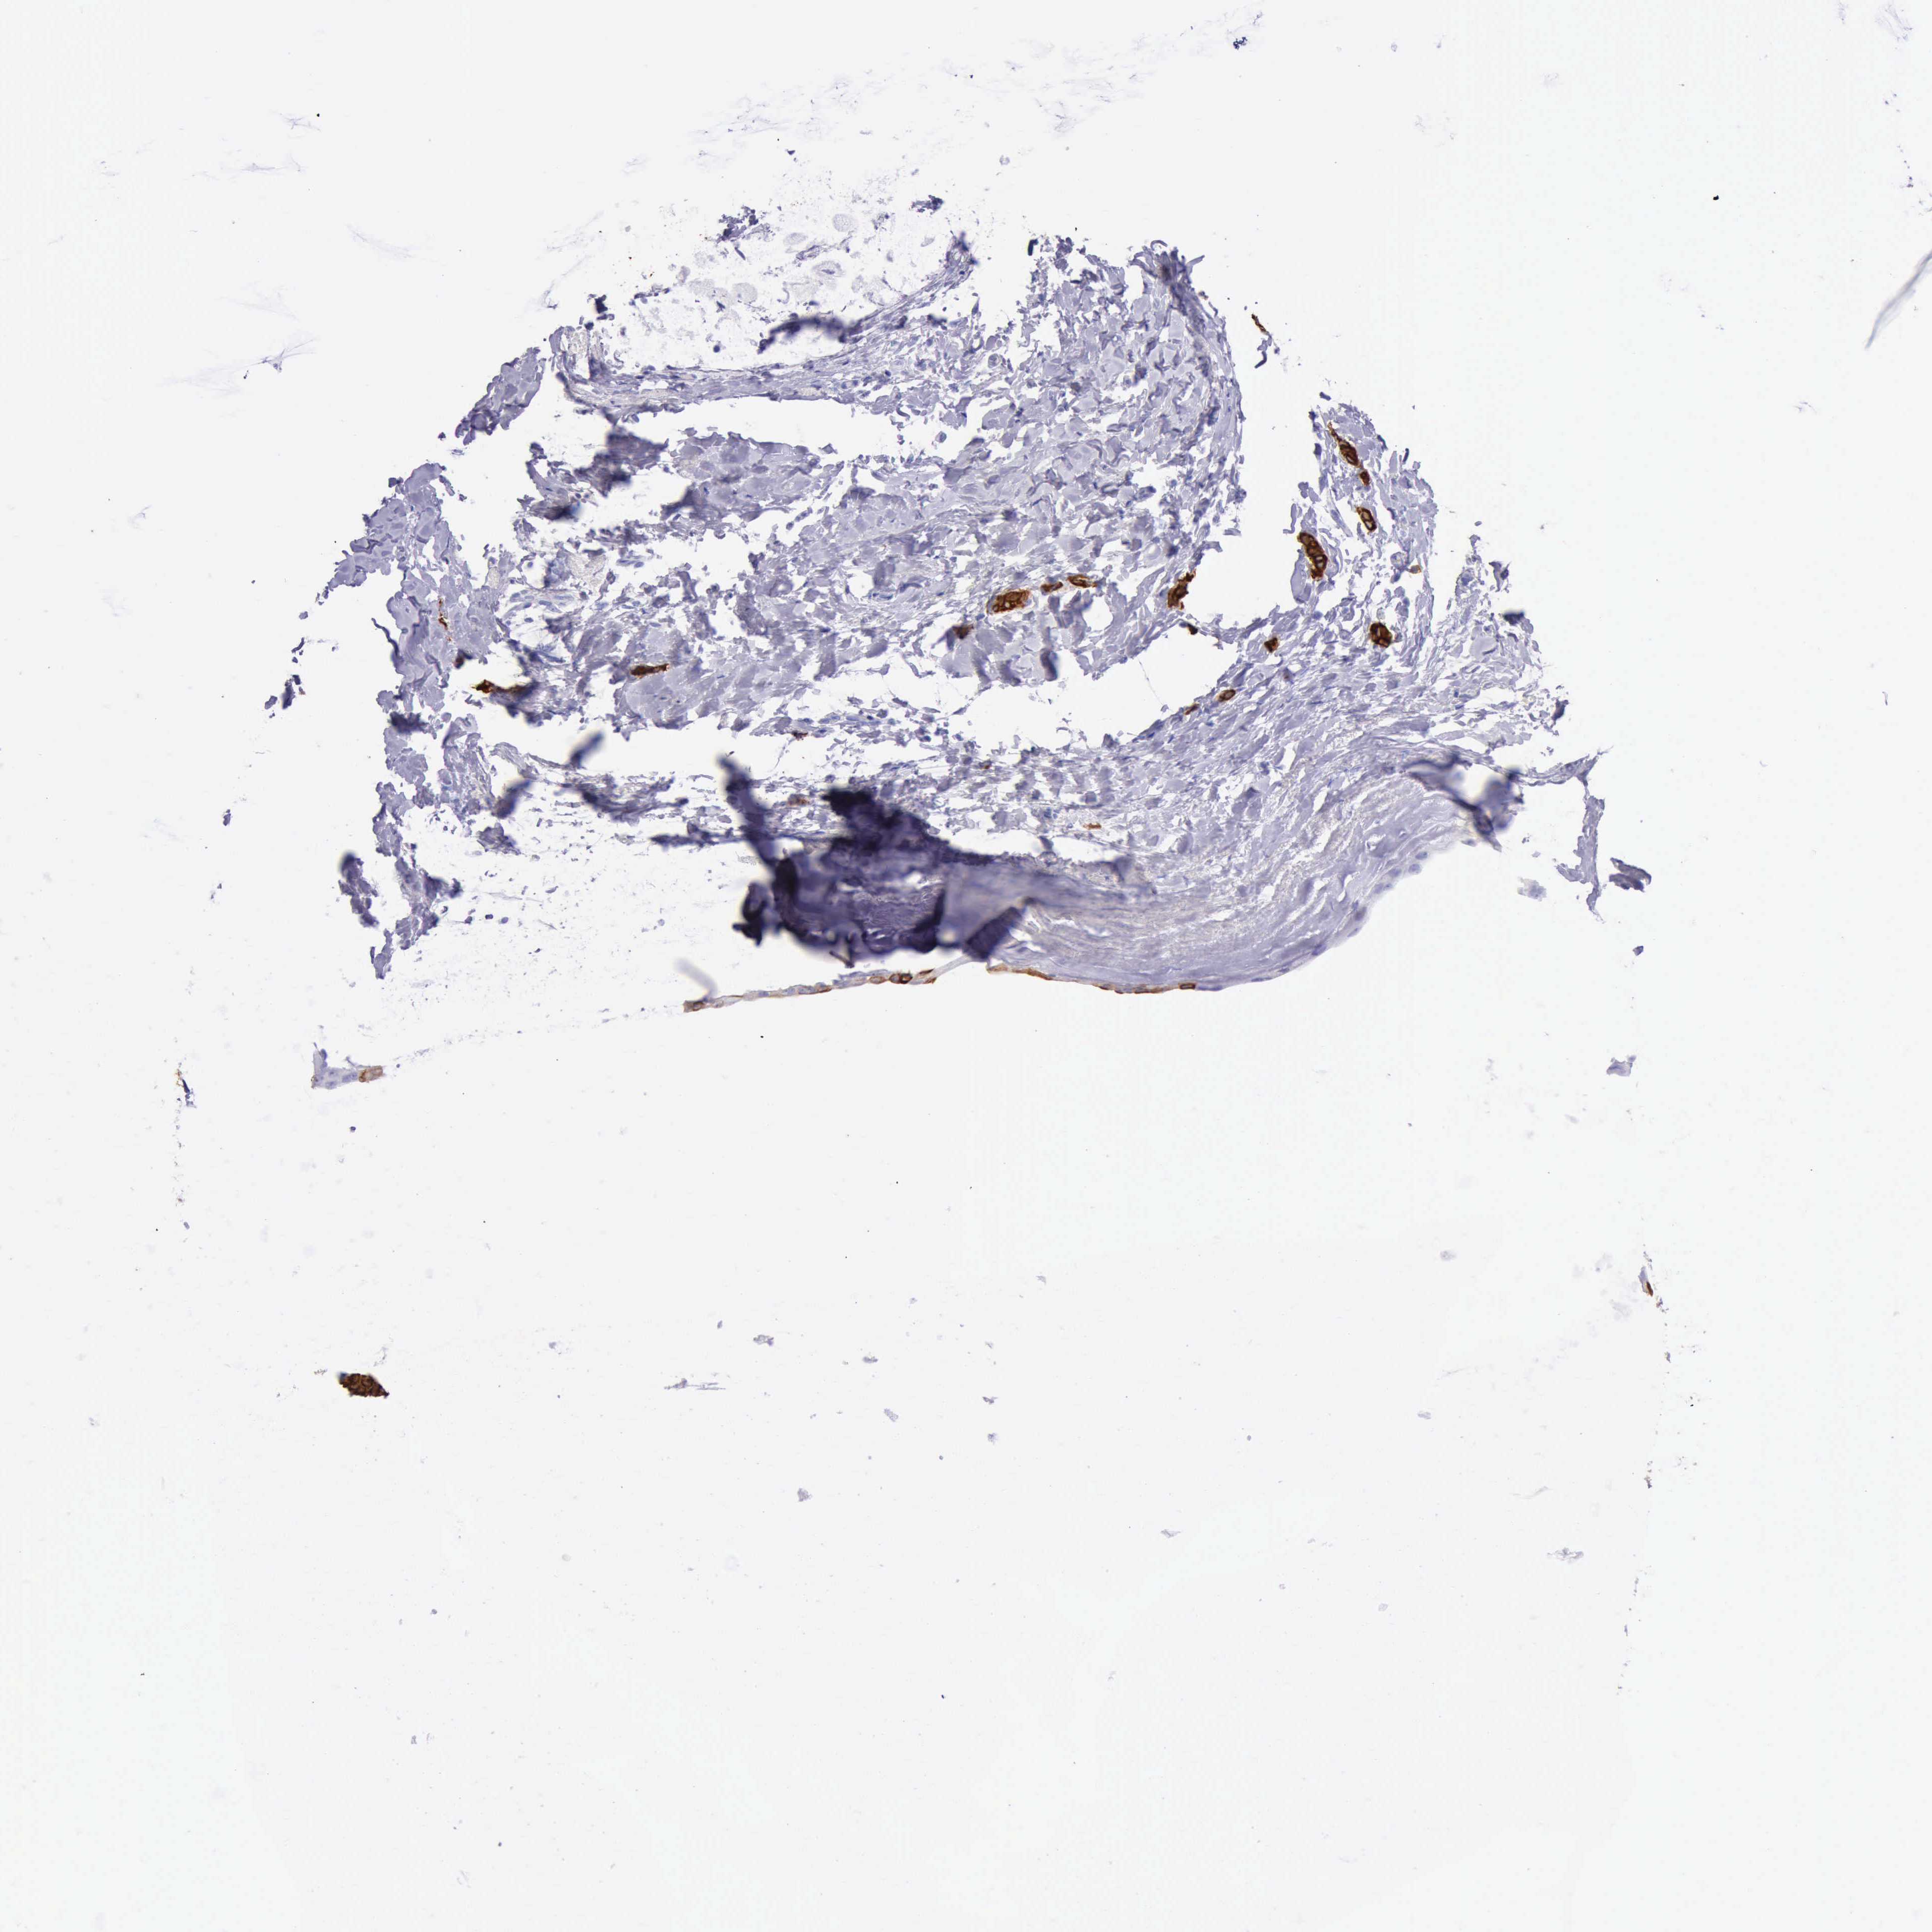

CANCER BREAST CANCER Show tissue menu

BRCA TCGA BRCA VALIDATION PROTEIN EXPRESSION